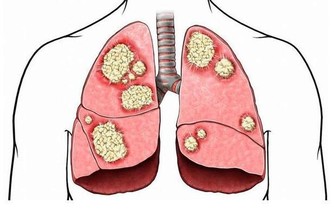

糖尿病引起的下肢血管病變和合併感染,是引起糖尿病足最主要的原因。

一方面,糖尿病性下肢血管病變,會導致足部局部缺血缺氧,延遲傷口癒合;

另一方面,高血糖使患者自身免疫功能下降,對感染的防禦能力降低,有利於細菌的繁殖。